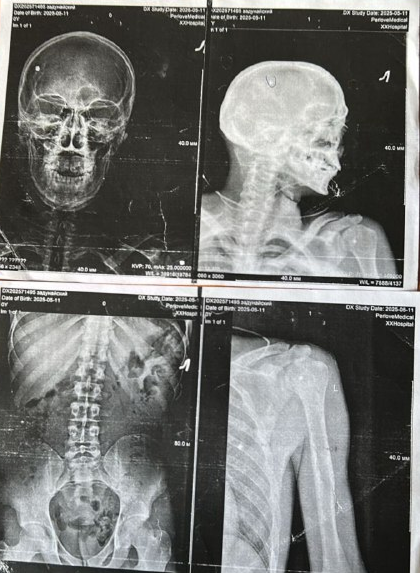

Основная сложность была в риске формального подхода со стороны членов ВВК. Они видят сотни людей и могут «обобщи» диагноз, не вдаваясь в детали пареза и трофических расстройств. Мы преодолели это за счет максимально полного пакета медицинских доказательств: результаты электромиографии (ЭМГ), снимки, подробные описания неврологического дефицита. Вторая сложность — необходимость подтверждения категории в вышестоящей комиссии. Мы заложили на это время и готовились изначально, что позволило пройти процедуру без задержек.

Итог зафиксирован в официальных документах. Заключение ВВК, который гласит: «В-ограниченно годен к военной службе». В Свидетельстве о болезни дана развернутая картина:

• Основной диагноз: Посттравматическая левосторонняя плечевая плексопатия... с глубоким парезом кисти... вследствие минно-взрывной травмы... с прямым указанием: «военная травма. Статья 27 пункт "б"».

• Второй диагноз: Посттравматический дефект нижней челюсти...«военная травма. Статья 56 пункт "в"».

Вышестоящая ВВК (филиал Главного центра) это заключение утвердила. На основании этого военнослужащий был уволен по состоянию здоровья с правом на все положенные выплаты, пенсию и реабилитацию.